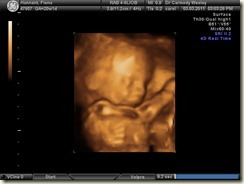

20 Week Scan (Morphology Scan)

At the 20 week stage you routinely have an ultrasound scan to check on the physical development of the baby. We have had all our ultrasounds done at the Wesley Fetal Medicine Unit in Brisbane which is a private clinic. Being a private clinic I think they are dotting their I’s and crossing their T’s a bit more than a public clinic would do, as part of their 20 week scanning procedure is to have a second sonographer double check the babies developmental features as well as every scan includes a DVD of the scan and 3d images.

I’m happy to report that everything is progressing perfectly with a really strong perfectly formed heart, kidneys, spine and lips plus everything else they checked.

The baby's feet measure 36mm at this point and its head is 50mm in diameter. The baby's length can no longer be measured as it longer than the width of the scanner, but judging by the length of the feet, legs, arms etc this babies appears to be 10 days in advance of where it should be. So in other words its either going to be a big baby or come a little bit earlier.

Anyways I have included a few of the 2d and 3d images from the scan.

We’ve decided to have non diagnostic 3/4d scan done in 7 weeks time where we should get some much nicer images as the baby should have some fat on it by then rather than being all skin and bones as it is now.